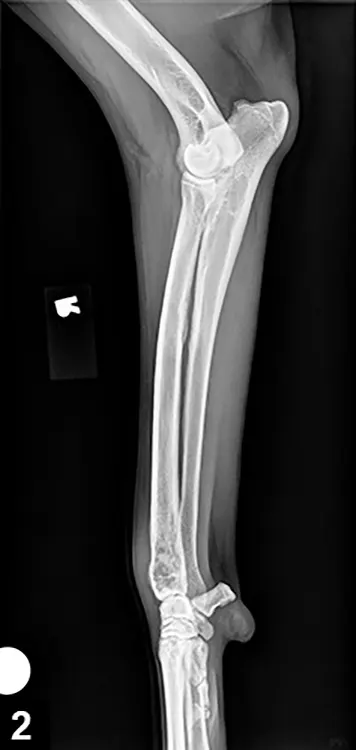

A lateral radiograph of a canine forelimb shows the humerus, radius, and ulna, highlighting a fracture in the mid-shaft of the radius. The image also includes a small marker indicating the area of interest for clinical assessment.

Evaluation of the primary site begins with good-quality radiography.

• Overall radiographic features can vary from bone lysis to almost entirely osteoblastic changes (Figure 2. Radiographic features of OSA).

• Cortical lysis is characteristic of OSA; severity may result in obvious areas of cortical discontinuity, resulting in pathologic fracture.

• Soft tissue extension with obvious soft tissue swelling is often seen, and new bone (tumor, reactive bone) may form in a palisading pattern perpendicular to or radiating from the cortical axis (ie, sunburst pattern).

• As the tumor invades the cortex, elevation of the periosteum occurs and new bone is laid down by the cambium layer, which provides triangular-appearing deposition of dense new cortical bone at the periphery of the lesion.

• This periosteal new bone (referred to as Codman’s triangle) is not pathognomonic for OSA.

• OSA rarely crosses articular cartilage.

• Extension into periarticular soft tissues puts adjacent bones at risk.

• Other radiographic changes include

• Loss of the fine trabecular pattern in the metaphysis

• Vague transition zone at the periphery of the medullary extent of the lesion instead of sharp sclerotic margin

• Regions of fine punctate lysis

• Lesion size, location, and duration will impact changes.

• These radiographic changes may also be typical of other primary and metastatic bone tumors.